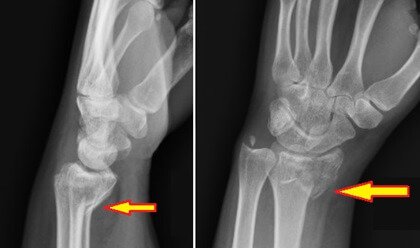

Smith Fracture X-ray

• X-rays: The primary diagnostic tool, Smith fracture X-rays of the wrist and forearm are taken from multiple angles (anteroposterior, lateral, and oblique views) to visualize the fracture, assess the angle and displacement, and check for any additional fractures. You can see a classic Smith Fracture X-ray here.